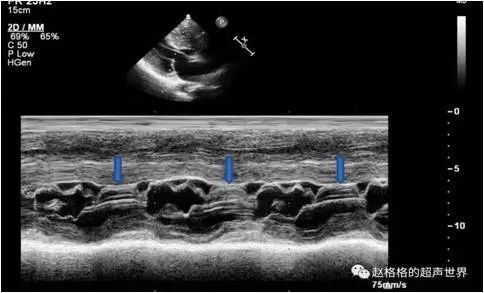

sam征超声表现,sam征

超声心动图 sam征小知识

sam征

sam征超声示意图

sam征超声心动图

sam现象超声图片

sam征阳性超声图片

二尖瓣sam征M型示意图